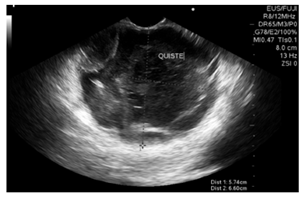

Se realizó una ultrasonografía endoscópica (EUS) biliopancreática que mostró una masa sólido-quística de 60 x 60 mm en la cola del páncreas, con un grosor de la pared de 4 mm, ecogenicidad mixta, sin componente vascular ni calcificaciones; y la presencia de una lesión de aspecto polipoide en su interior de 30 mm (Figura 2). Se realizó una punción con aguja fina (FNA) con aguja n.° 19 G (Wilson Cook) (Figura 3) y se obtuvieron 4 cc de líquido mucoide con múltiples fragmentos blanco-amarillos, para el procesamiento de citología y bloque celular. La coloración hematoxilina-eosina mostró células epiteliales escamosas y mononucleares, tejido necrótico, hemorragia reciente y antigua con escasas células glandulares sin atipia. No había evidencia de tejido pancreático. El procesamiento del ACE no se realizó porque no había disponibilidad de dicho recurso en la institución.

La EUS es la herramienta de evaluación ideal. Tiene un bajo riesgo y permite la obtención de biopsias. Los criterios para diferenciar quistes mucinosos (septos macroquísticos o masas adyacentes) de los no mucinosos (uniloculares, panal de abejas o pared engrosada), tienen sensibilidad y especificidad bajas, 56% y 45%, respectivamente; y la precisión diagnóstica es del 51% 12. La superposición de características morfológicas entre los diferentes tipos de quistes es la razón de la baja precisión a pesar de la adecuada visualización de las estructuras 13.

La presencia de lesiones sólidas intraquísticas, irregularidad y engrosamiento de la pared o masa sólida adyacente son signos sugestivos de malignidad 2. La falta de comunicación con el conducto pancreático los diferencia de las NMPI 14.